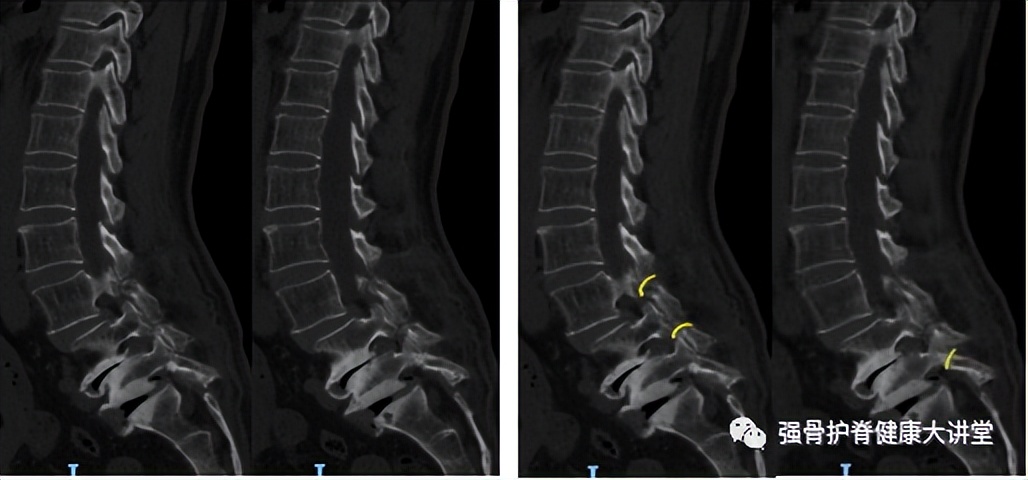

图1

图2 图2

图1、2 为63岁女性,诊断为腰椎峡部裂滑脱(L3-L5),红色线为CT矢状位右侧峡部裂位置,黄色线为CT矢状位左侧峡部裂位置。